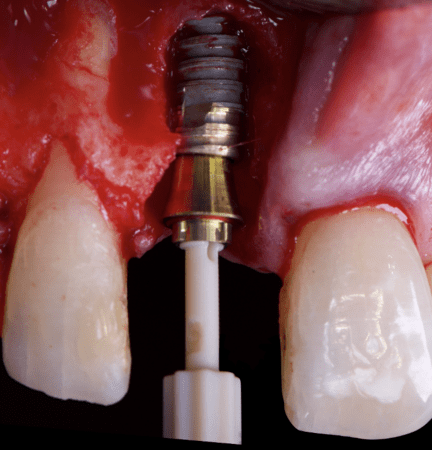

The surgical protocol began with the atraumatic extraction of tooth 1.1 to preserve as much of the alveolar socket as possible. Immediately following extraction, an N1 implant was placed into the socket using a guided surgical approach to ensure ideal three-dimensional positioning. The “one abutment one time” technique was applied to minimize soft tissue manipulation during the healing phase, which is particularly important in esthetic areas.

Given the significant buccal defect, guided bone regeneration (GBR) was performed simultaneously. A mixture of autologous bone and creos™ xenogain™ was applied to the defect and covered with a resorbable creos™ membrane to restore ridge width and support the buccal contour. In addition, a connective tissue graft was harvested and placed in the vestibular region to increase the thickness of keratinized mucosa. This combined approach addressed both hard and soft tissue deficiencies, providing the biological foundation for a stable and esthetic outcome.

On the same day as the surgery, an immediate-load provisional crown was delivered. This restoration was fabricated in acrylic resin and screw-retained on the implant, following the “one abutment one time” principle. The provisional crown was carefully adjusted to avoid occlusal loading while supporting the peri-implant soft tissue architecture during the healing phase.